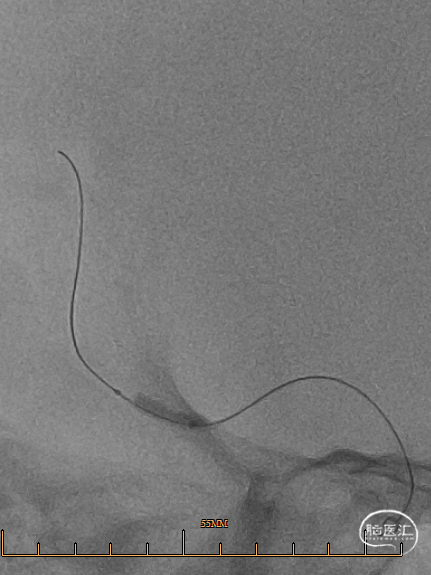

诊疗经过